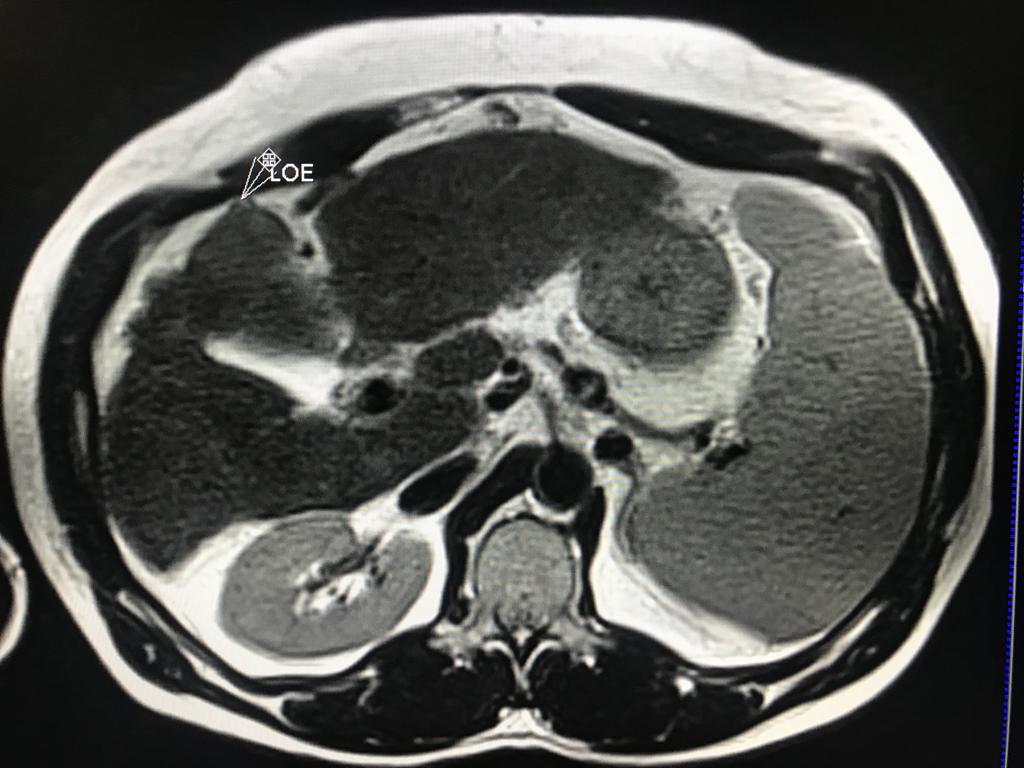

Masculino de 52 años, con cirrosis hepática. La elastografía ecográfica evidencia fibrosis Categoría F3 según escala de METAVIR y la presencia de múltiples nodulaciones, que en su mayoría son menores a 2 cm.

En este contexto, toda nodulación mayor de 1 cm, debe ser evaluada idealmente con RM trifásica con secuencia de Difusión , para discriminar si se trata de nódulos de regeneración , nódulos displásicos o hepatocarcinoma.

En el presente caso, encontramos una lesión típica de hepatocarcinoma en el segmento 5 ( hiperintensa en T2, restringe en la Difusión con ADC bajo. Realza heterogéneamente postcontraste EV, con wash out y presencia cápsula tardía).

El objetivo es identificar dentro de la multifocalidad de nódulos , un hepatocarcinoma precoz o de pequeño tamaño , cuando la posibilidad de tratamiento con intención curativa es viable , a pesar de la cirrosis.